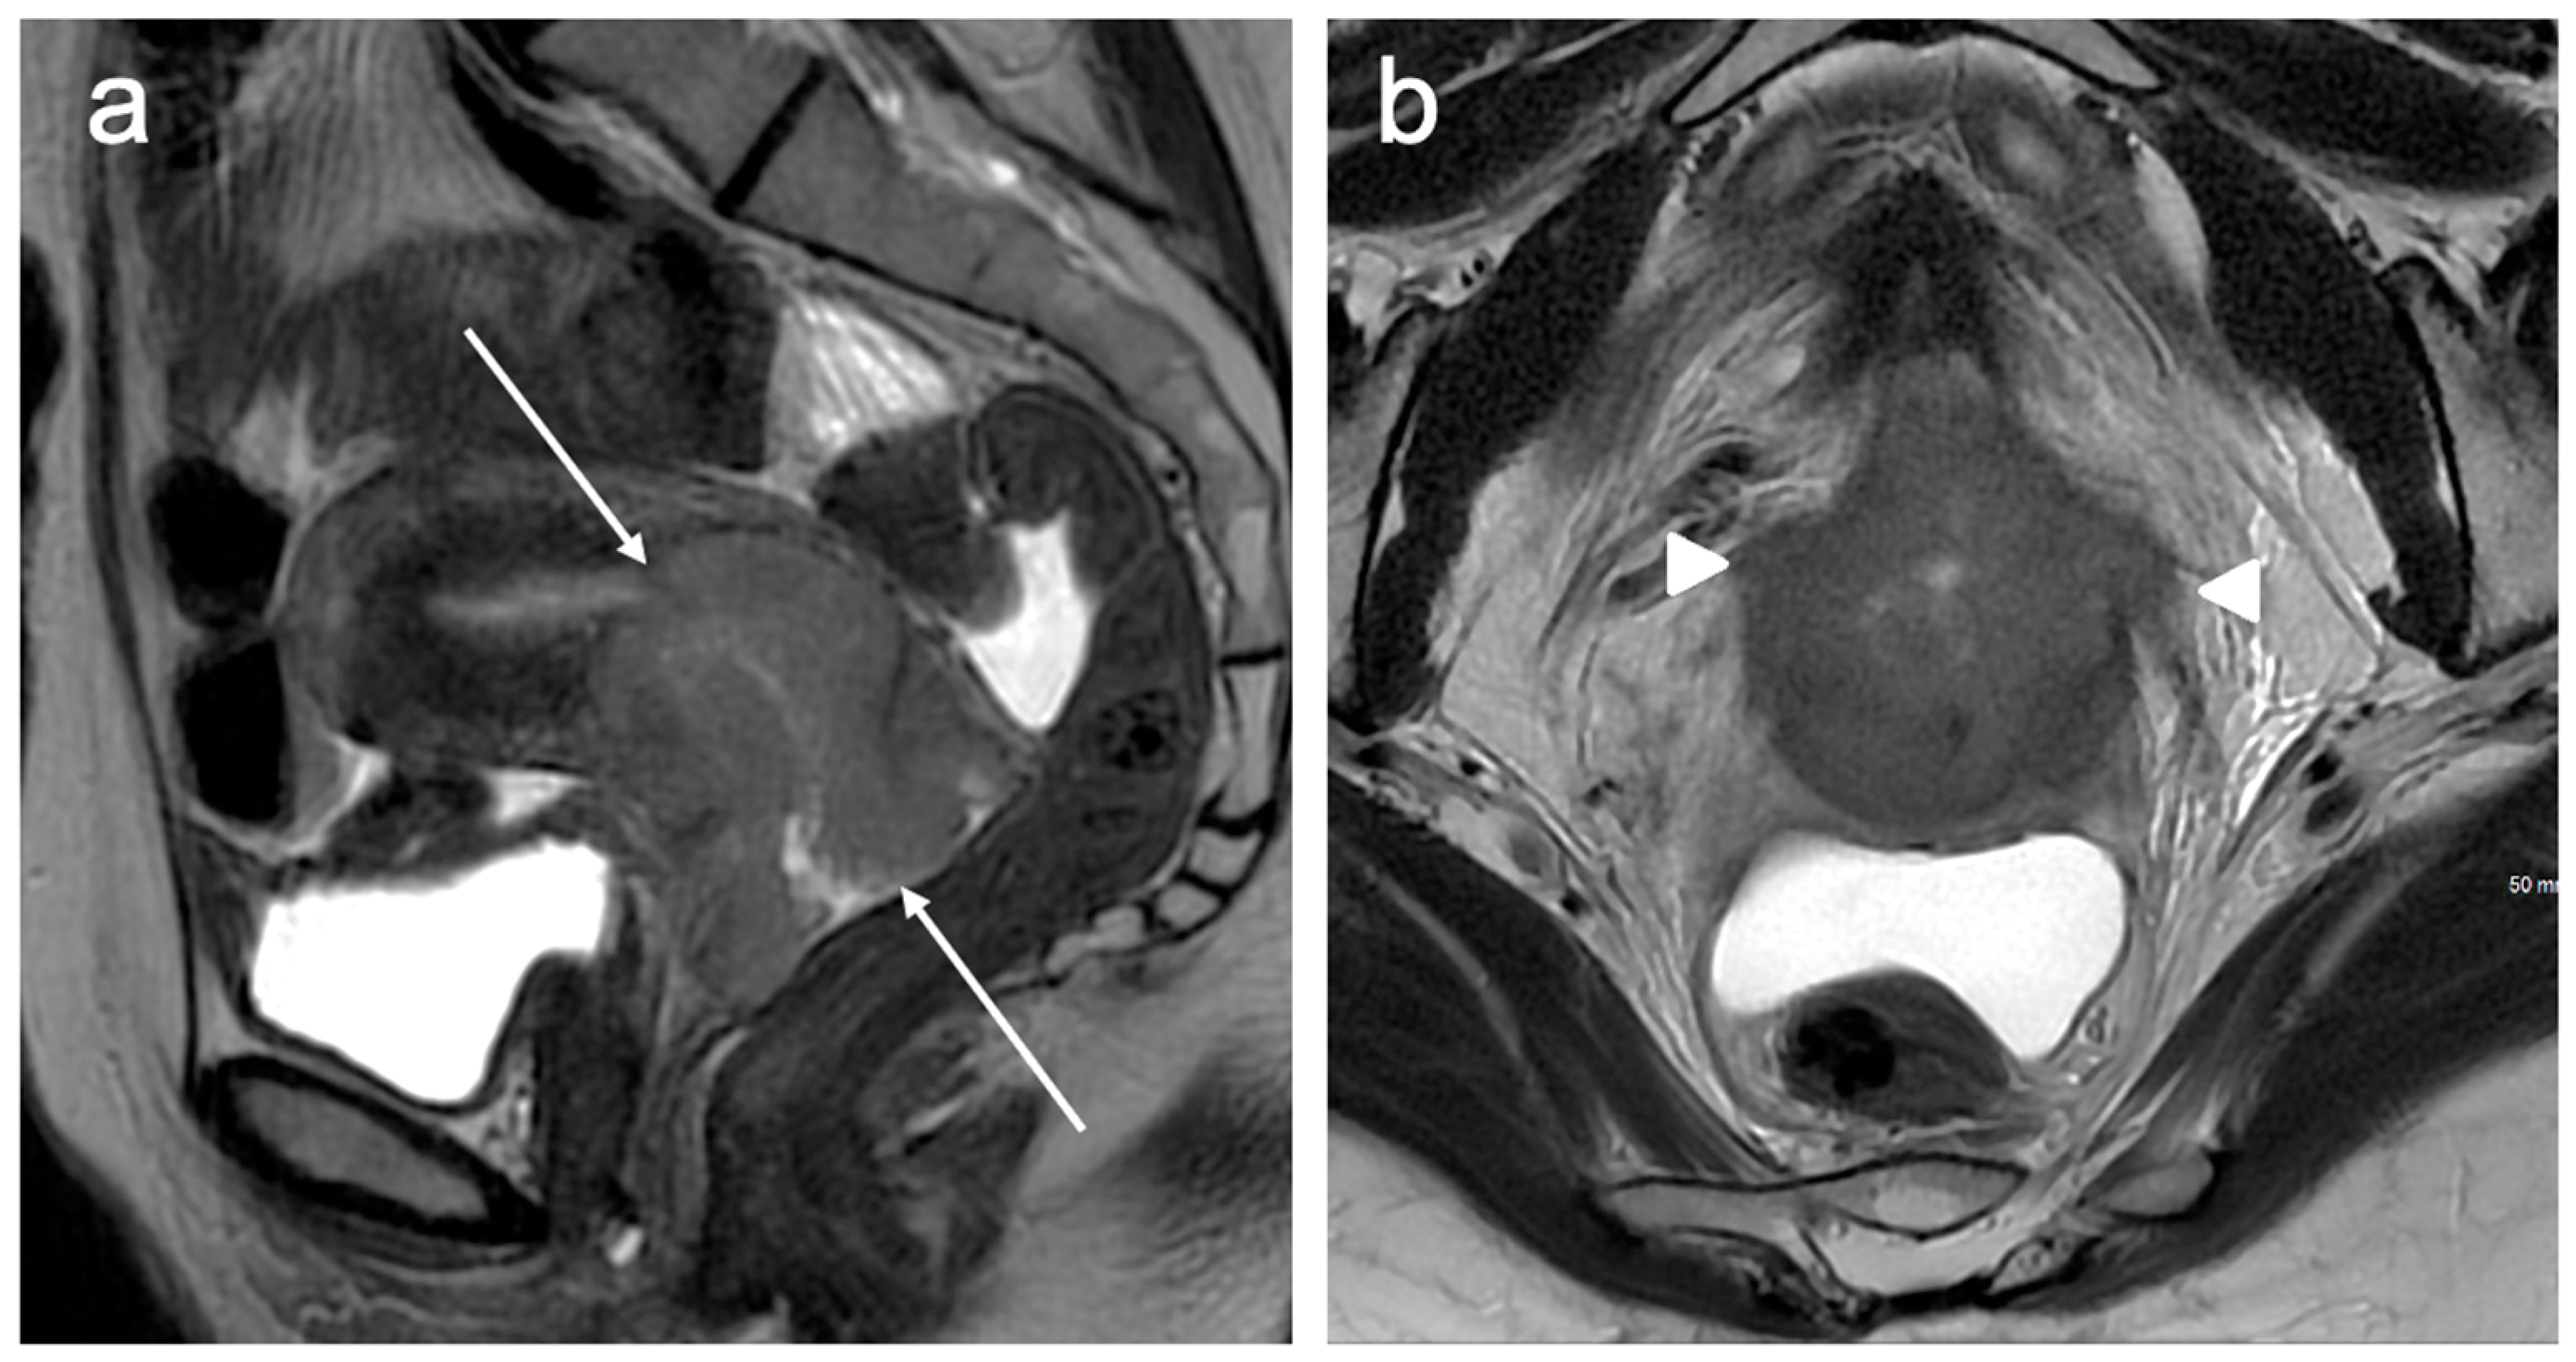

| IIB | With parametrial invasion but not up to the pelvic wall |